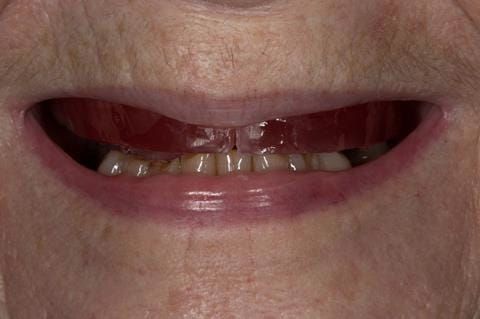

Following consultation and second discussion appointment the patient chose to have option 2 namely, a window denture - maxillary cobalt chromium based partial denture. The clinical situation and treatment process is shown in detail below with photographs. The patient was successfully rehabilitated with this and her quality of life considerably improved. The clinical work was provided by Finlay and the technical work by Rowan.